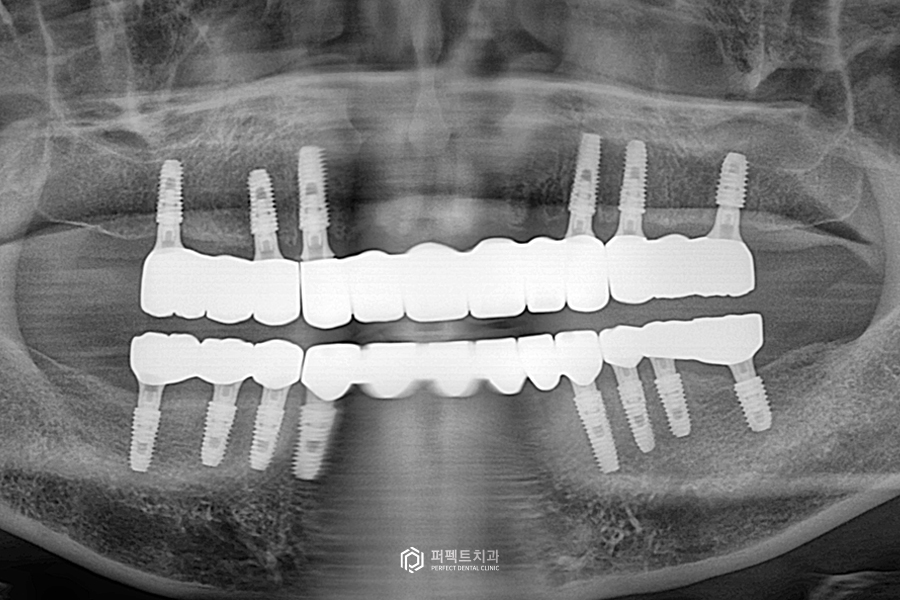

치료 후 엑스레이

심어놓은 임플란트에 치아가 다 걸려있습니다. 3piece로 제작을 했는데요. 세 덩어리로 나눠서, 총 6piece로 제작이 되었습니다.

구강사진을 보시면 지르코니아 라는 재료를 이용해 전체를 수복했고, 교합도 깨끗하게 잘 물리도록 완성이 되었습니다.